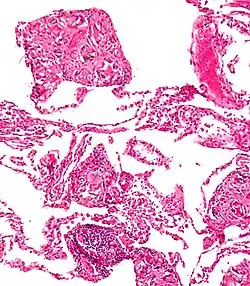

Gastrointestinal tract

One of the most common locations for a foreign body is the alimentary tract.

It is possible for foreign bodies to enter the tract from the mouth or rectum.

Both children and adults experience problems caused by foreign objects becoming lodged within their bodies. Young children, in particular, are naturally curious and may intentionally put shiny objects, such as coins or button batteries, into their mouths. They also like to insert objects into their ear canals and nostrils.[1] The severity of a foreign body can range from unconcerning to a life-threatening emergency. For example, a coin causes local pressure on the tissue but generally is not a medical emergency to remove. A button battery, which can be a very similar size to a coin, generates hydroxide ions at the anode and causes a chemical burn in two hours.[2] An ingested button battery that is stuck in the esophagus is a medical emergency. In 2009, Avolio Luigi and Martucciello Giuseppe showed that although ingested nonmagnetic foreign bodies are likely to be passed spontaneously without consequence, ingested magnets (magnetic toys) may attract each other through children's intestinal walls and cause severe damage, such as pressure necrosis, perforation, intestinal fistulas, volvulus, and obstruction.[3]